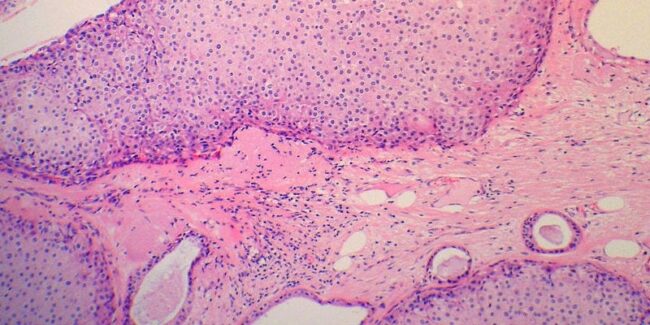

1. This randomized controlled trial of women with metastatic triple-negative breast cancer reports that patients who were received atezolizumab with nab-paclitaxel had longer periods of progression-free survival compared to patients who received placebo plus nab-paclitaxel therapy.